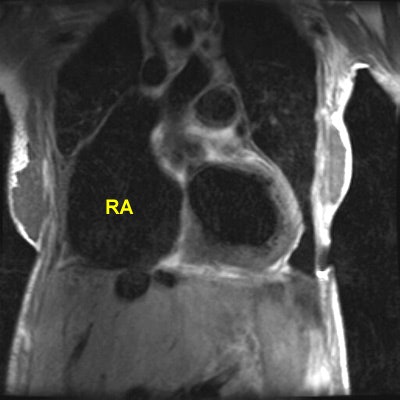

Rheumatic Fever

The patient shown below had a long history of valvular heart disease secondary to rheumatic fever. Both mitral and tricuspid valves were involved. There is massive right atrial (RA) dilatation. The left atrium is also massively dilated. Increased signal within the left atrium is related to slow flow.